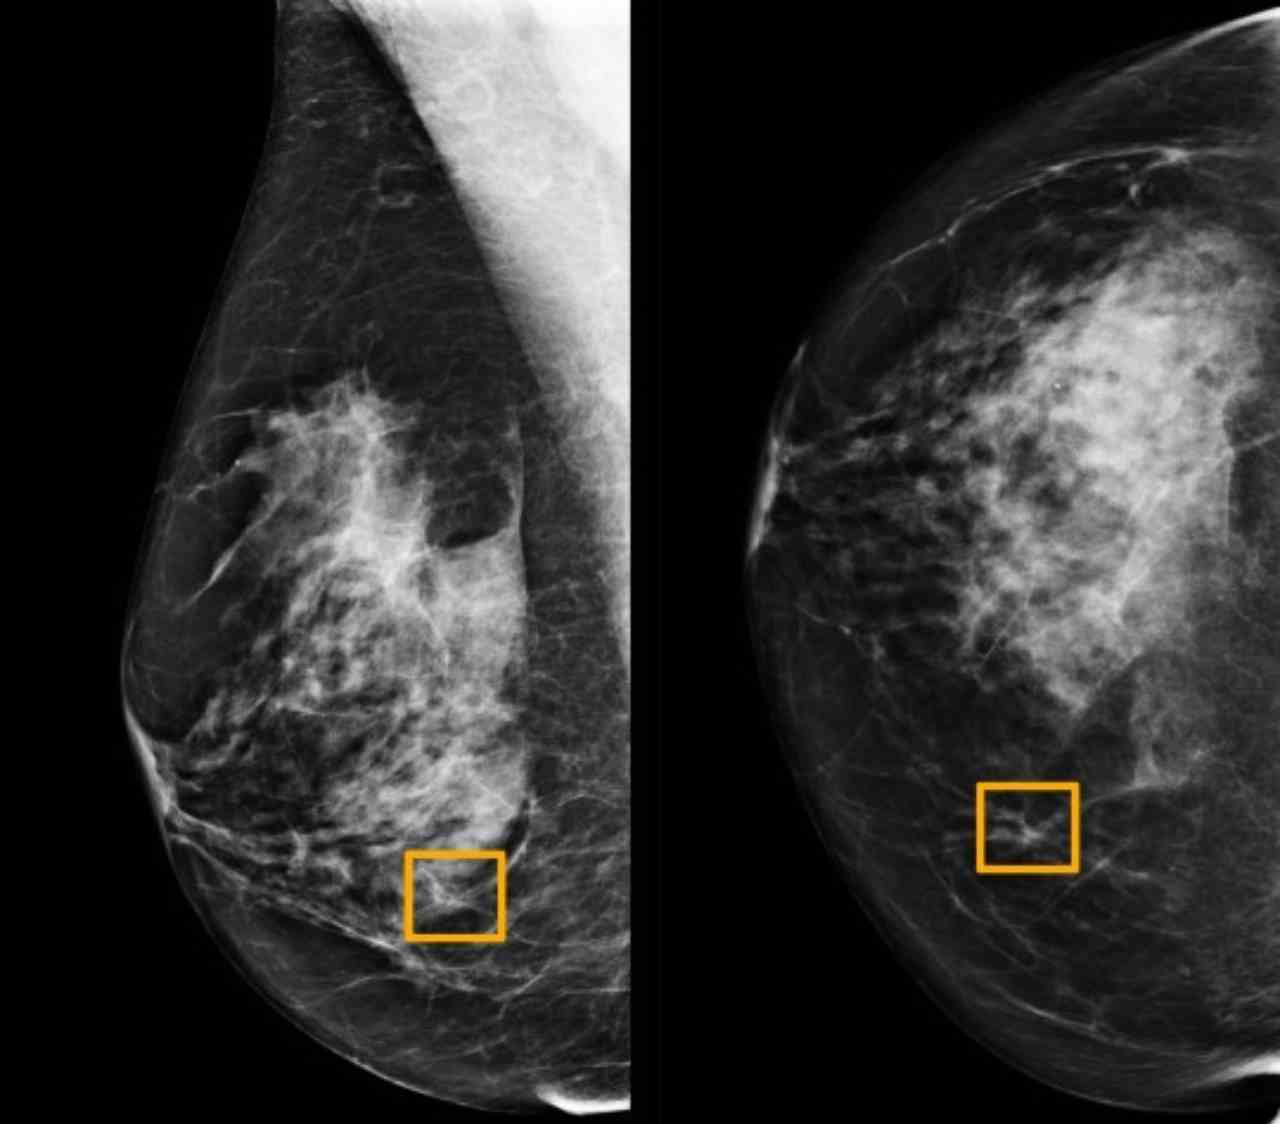

Una nuova ricerca di scienziati britannici e americani è stata paragonata ad un controllo ortografico per la scrittura di e-mail. Difatti gli studiosi in questione hanno sviluppato un algoritmo che potrebbe salvare potenzialmente migliaia di donne, individuando tumori che i radiologi potrebbero altrimenti non riuscire a scovare in tempo. I tumori non diagnosticati possono portare a ritardi potenzialmente letali nel trattamento. Questa svolta potrebbe anche aiutare a prevenire i cosiddetti falsi positivi durante lo screening di routine, risparmiando alle donne un intervento chirurgico non necessario su aree che i medici sospettavano erroneamente di essere cancerose.

Lo studio ha rilevato che i rilevamenti errati – eventualità che può purtroppo verificarsi – sono così ridotti da circa uno su diciotto a quasi uno su cento. Il co-autore dello studio, il dott. Mozziyar Etemadi, assistente professore di anestesia presso la Northwestern University di Chicago, ha spiegato: “Questo è un enorme progresso nell’ambito di potenziali diagnosi precoci della malattia. Il cancro al seno è una delle maggiori cause di mortalità nelle donne. Trovarlo in anticipo significa che può essere più piccolo e più facile da curare. In tutto ciò sono state compiute osservazioni su 25.856 donne non identificate da tre fondi ospedalieri. Il risultato è che ci sono stati molti meno casi in cui il cancro veniva erroneamente identificato o non individuato. Con i risultati poi pubblicati sulla rivista specializzata di settore ‘Nature’.

La mammografia è lo strumento di screening più utilizzato, ma è difficile diagnosticare il cancro dalle sue immagini. Complessivamente, i radiologi mancano una tempestiva individuazione della malattia in un caso ogni cinque. Il doppio rispetto a quello riportato nello studio. Un altro autore dello studio, Scott McKinney, un ingegnere informatico presso Google Health in California, ha dichiarato quanto segue. “I computer sono davvero efficienti in questi compiti. Speriamo che un giorno questo strumento per i radiologi diventi onnipresente come il controllo ortografico per la scrittura di e-mail.” Si spera che gli strumenti di intelligenza artificiale possano supportare il processo decisionale e quindi ridurre il carico di lavoro del personale.